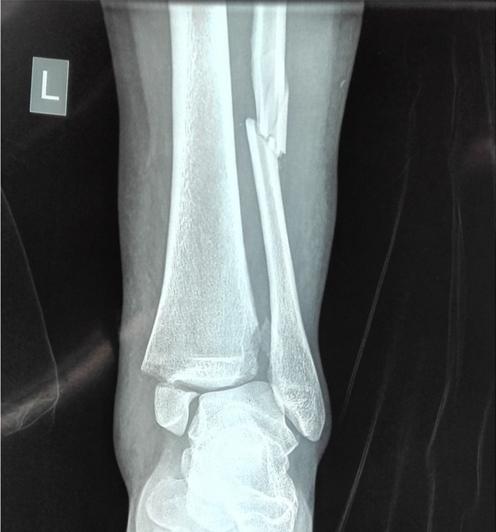

辅助检查:X光提示右踝骨折伴后脱位。

临床诊断:右侧踝关节骨折脱位

右踝骨折伴后脱位